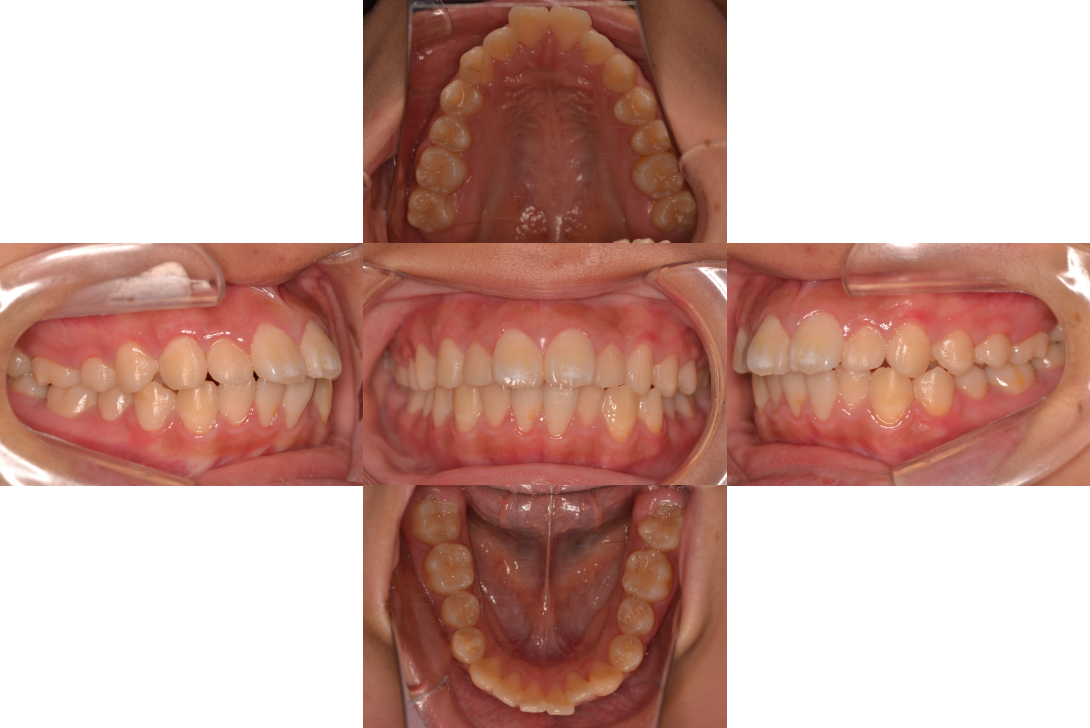

上顎前突(出っ歯)を抜歯とDBSで改善した症例

※DBSとはダイレクトボンディングシステムと呼ばれており、ブラケットにワイヤーを通して歯を動かしていく矯正治療です。

患者情報

16歳女性

主訴

口元下げたい

行った治療内容

上下顎両側4番抜歯、DBS

治療のリスク

歯根吸収、前歯部歯肉退縮

治療期間

動的治療期間2年9か月

※ クリックして拡大することができます。